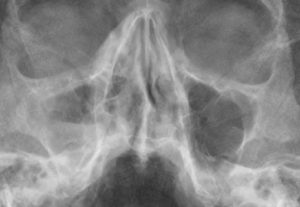

Взрослых специалист направляет на рентгеноскопию и ультразвуковое исследование. При недостатке информации назначает пункцию. Детям и беременным рентген противопоказан. Вместо него используют метод диафаноскопии, изучая области гайморовых пазух с помощью лампы Геринга.

- рентген-исследование пазух;

Локализацию болезни проще всего обнаружить на рентгеновском снимке. Патология отображается на нем в виде темных пятен различного объема.